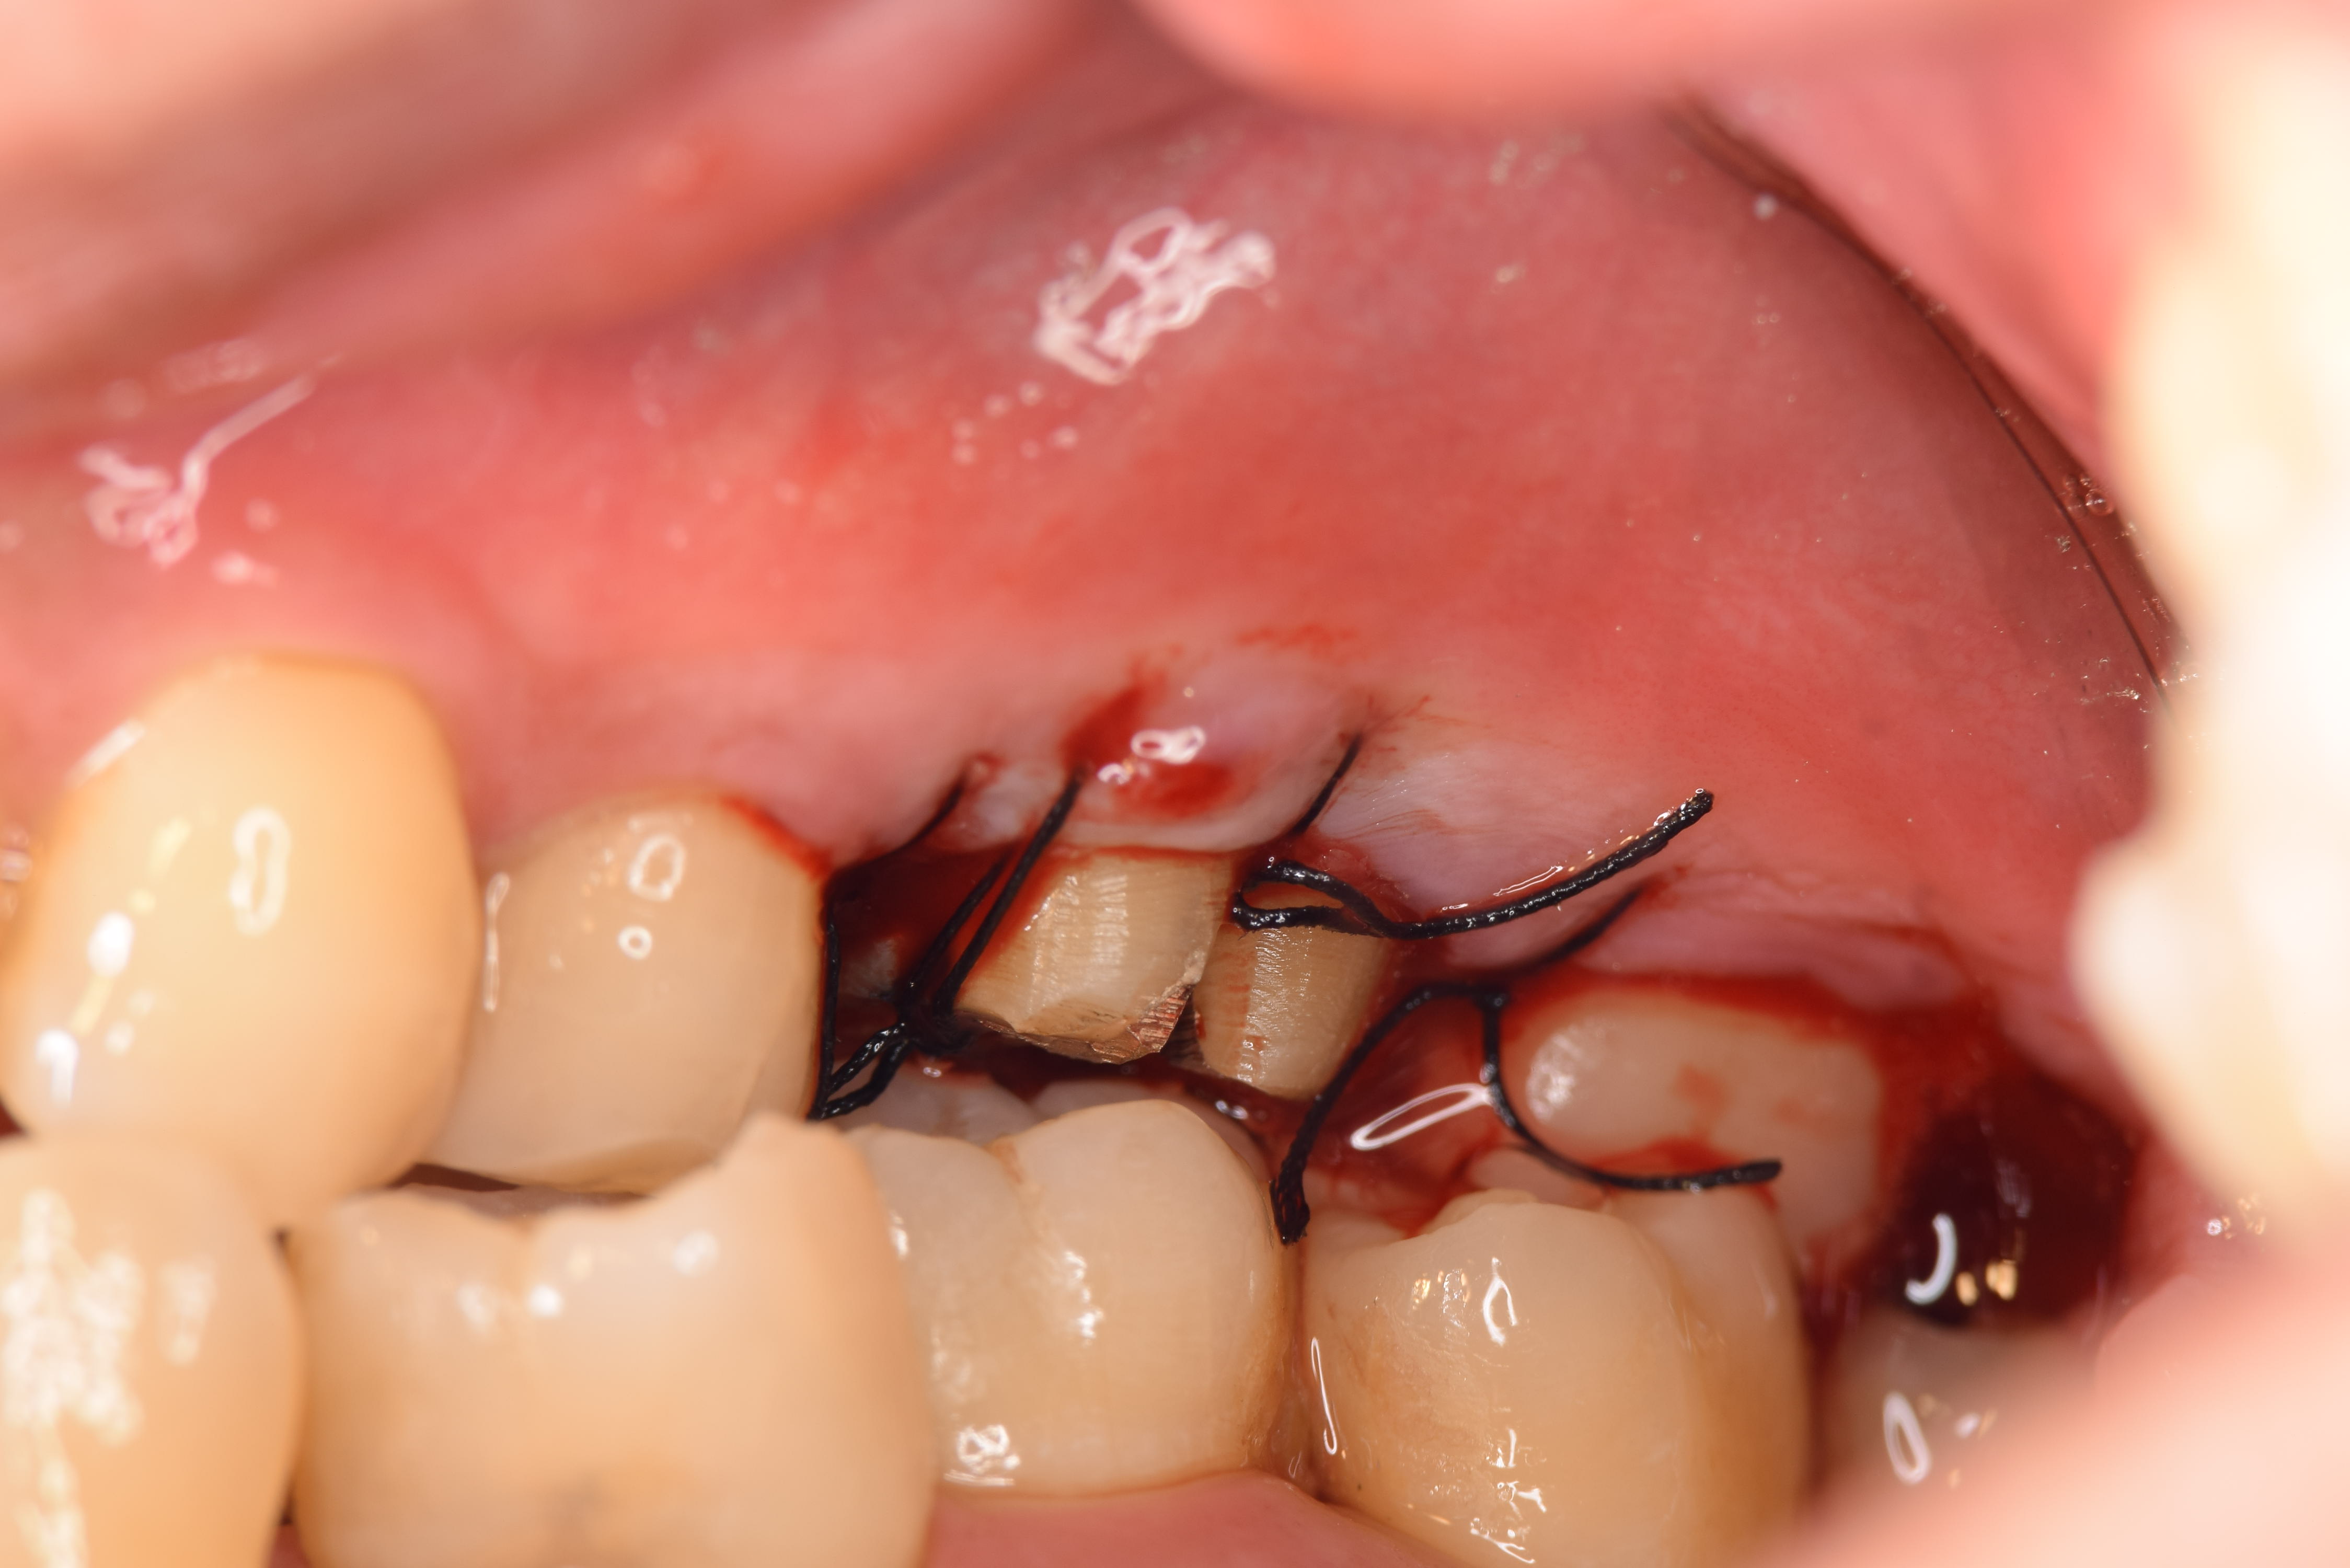

術前の状態です。小さな膿の袋があります。(ミラー像)

歯を分割し、一度抜いた状態です。

抜いた状態で骨の中にある感染源と歯根に付着している細菌(バイオフィルム)を除去します。

感染経路となっている根の先をMTAセメントで封鎖します。この操作を逆根管充填と言います。

再植完了です。